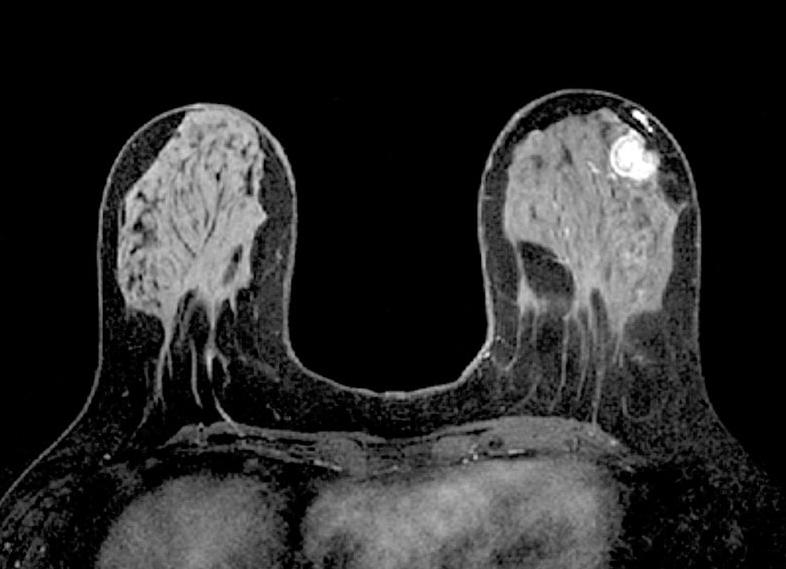

МРТ молочных желез с контрастом и без контраста

Магнитно-резонансная томография молочных желез может проводиться с контрастом либо без контраста. Без контраста МРТ проводят для получения следующей информации:

• о плотности тканей молочной железы;

• о наличии расширений млечных потоков;

• о наличии кист;

• о наличии гематом;

• о наличии разрывов либо утечек грудных имплантатов.

Использование контрастного вещества при проведении МРТ позволяет осуществить следующее:

• выявить наличие патологических образований в груди;

• распознать и отличить доброкачественные новообразования от злокачественных;

• определить размер, а также локализацию возможного патологического образования;

• рассмотреть увеличение лимфатических узлов.

МРТ молочной железы с контрастированием подразумевает использование специального контрастного вещества. Контраст вводится внутривенно, чтобы визуализировать новообразования, а также показать, какие именно сосуды их питают. Также контраст позволяет определить характер опухоли (доброкачественный либо злокачественный). Использование контрастного усилителя повышает информативность магнитно-резонансной томографии при определении рака груди до 95%.